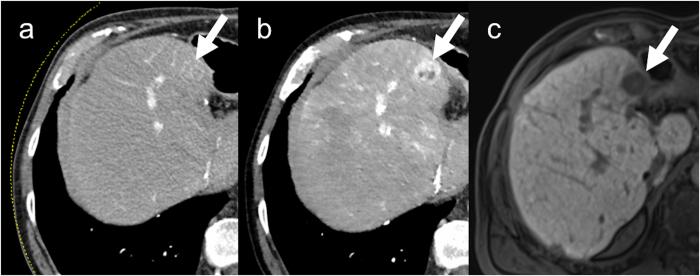

Aim of this study was to compare low tube voltage computed tomography (80 kV) of the liver using iterative image reconstruction (SAFIRE) with standard computed tomography (120 kV) using filtered back-projection (FBP) for the detection of hepatocellular carcinoma (HCC). 46 patients (43 men) with 93 HCC confirmed by 3 T MRI with Gd-EOB-DPTA, in inconclusive cases combined with contrast-enhanced ultrasound, underwent dual-energy CT. The raw data of the 80 kV tube was reconstructed using the iterative reconstruction algorithm SAFIRE with two strengths (I3 and I5). The virtual 120 kV image data set was reconstructed using FBP. The CT images were reviewed to determine the lesion-to-liver contrast (LLC), the lesion contrast-to-noise ratio (CNR) and the sensitivity. The LLC (57.1/54.3 [I3/I5] vs. 34.9 [FBP]; p ≤ 0.01), CNR (3.67/4.45 [I3/I5] vs. 2.48 [FBP]; p < 0.01) and sensitivity (91.4%/88.2% [I3/I5] vs. 72.0% [FBP]; p ≤ 0.01) were significantly higher in the low-voltage protocol using SAFIRE. Therefore, low tube voltage CT using SAFIRE results in an increased lesion-to-liver contrast as well as an improved lesion contrast-to-noise ratio compared to FBP at 120 kV which results in a higher sensitivity for the detection of HCC.

本研究旨在比较使用迭代重建(SAFIRE)的低管电压(80kV)肝脏计算机断层扫描(CT)与使用滤波反投影(FBP)的标准 CT(120kV)在检测肝细胞癌(HCC)方面的效果。46 例(43 例男性)患者,其 93 个 HCC 经 3T MRI 检查结合钆塞酸二钠(Gd-EOB-DPTA),对诊断不确定的病例结合增强超声检查,进行了双能 CT 检查。80kV 管的原始数据使用迭代重建算法 SAFIRE 进行重建,具有两种强度(I3 和 I5)。虚拟 120kV 图像数据集使用 FBP 进行重建。对 CT 图像进行了回顾性分析,以确定病灶与肝脏的对比(LLC)、病灶对比噪声比(CNR)和灵敏度。低电压协议使用 SAFIRE 时 LLC(57.1/54.3[I3/I5]比 34.9[FBP];p≤0.01)、CNR(3.67/4.45[I3/I5]比 2.48[FBP];p<0.01)和灵敏度(91.4%/88.2%[I3/I5]比 72.0%[FBP];p≤0.01)显著更高。因此,与 120kV 时的 FBP 相比,使用 SAFIRE 的低管电压 CT 可提高病灶与肝脏的对比度,以及病灶对比噪声比,从而提高 HCC 的检测灵敏度。